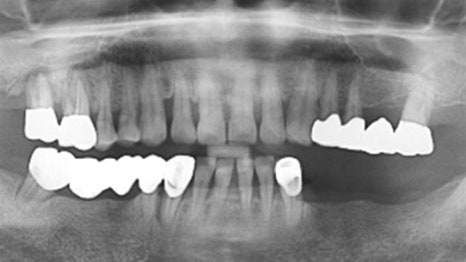

사례

상악(윗니) 틀니를 사용하시던 환자분이

씹는 힘이 약해 대학병원에서 전체 임플란트를

권유받으셨습니다.

비용 부담으로 본원에 내원하셨고,

당뇨 관리와 식생활 개선을 함께 진행한 후

24개를 식립하였습니다.

수술 후에도 내과 협진을 유지하여 혈당을 조절하고

전신 건강이 회복될 수 있도록 도왔습니다.